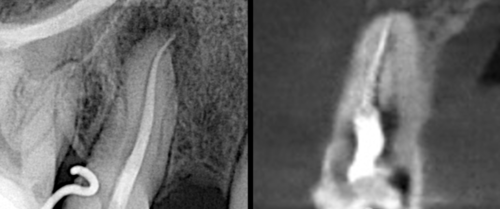

正常情况下拔牙术后疼痛适的通常3-7天消失,3个月左右拔牙窝内会长出新的骨质形成骨性愈合。而在双膦酸盐的药物影响下,牙槽骨的改建受到干扰,无法正常的完成破骨-新骨形成的过程,从而导致拔牙创经久不愈并继发感染,最终演变为颌骨骨坏死,甚至有使用过双膦酸盐药物的患者,在没有进行拔牙手术的情况下,仍然因为牙齿的发炎诱发颌骨骨坏死,这都给病人造成长期的痛苦及严重心理的负担。

随着双膦酸盐类药物的广泛应用,相应的药物不良反应事件相继出现。近来有实验证实包括唑来膦酸在内的BP 药物可能会使颌骨坏死,并把这种现象称为双膦酸盐相关性颌骨坏死(BONJ) 。

根据此标准,BONJ 的诊断并不困难。目前,BONJ 的发生机制尚不清楚,有人认为可能与BP 药物抑制破骨细胞功能、诱导凋亡、微血管栓塞、创伤和感染等因素有关。结合相关文献,BONJ 静脉和口服药物的发病率分别约为1%和0. 002%。目前,BONJ 尚缺乏理想的治疗方法,临床上主要使用刮除死骨、冲洗创面,高压氧等方法治疗。但是疗效并不确切,有相当大比例的患者病情迁延不愈,因此BONJ 重在预防。